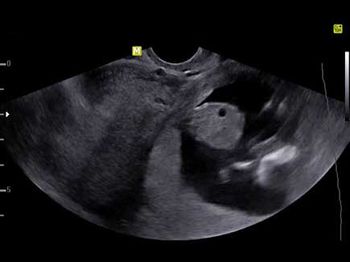

Challenge your diagnostic skills: What’s odd about this 16-week pregnancy?